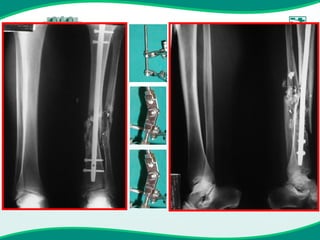

Fixador monoaxial de tíbia conversão

Fixador monoaxial Orthofix Fratura do terco distal da t’ibia